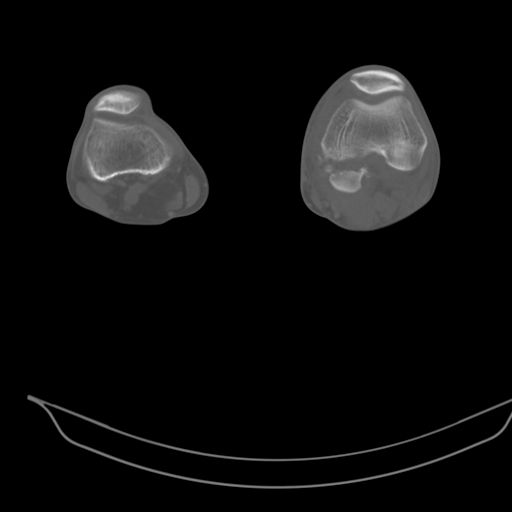

Качественные только исходные рентгенограммы (вышлю или завтра или в понедельник). Все последующие рентгенисследования были малоинформативны

(в т.ч. и последние снимки). КТ-исследование делалось 3 или 4 дня назад...

CT shows major bony fragments which are markedly rotated .With this amount of bony damage,you probably should attempt to get reasonably loooking knee with ORIF and thn if he needs a TKR due to pain a few years from now, then tleast you have something looking like a knee that you can replace rather than having to use revision knee for a primary TKR now. 4 weeks is not too long .what is the condition of soft tissues?

При внутрисуcтавных переломах трехмерные (3D) изображения, кроме красивого снимка, не дают полную информацию о состоянии отломков, самыми информативными являются корональные срезы на КТ и обычная длинная ренгенограмма конечности для сравнения оси конечности.

Фронтальные внутрисуставные переломы мыщельков бедра, так называемые Hoffa fracture, не частые, но встречающиеся переломы, в основном они связаны с травмой высокой энергией.